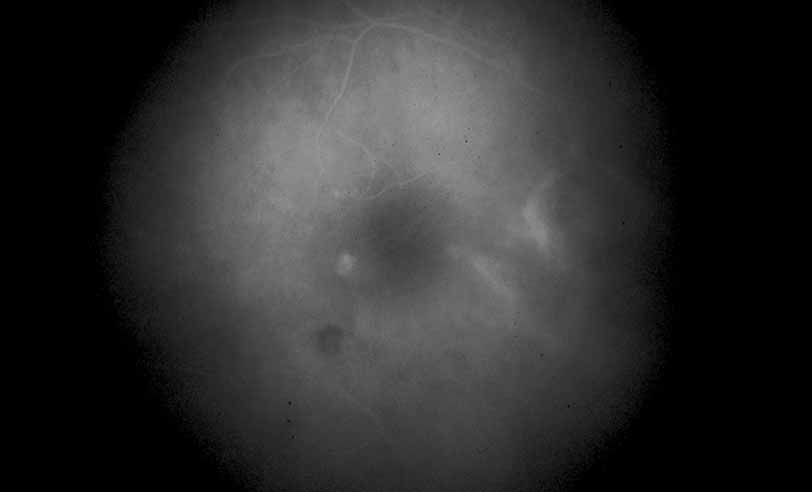

Fig. 29 Serpiginous choroiditis. ICG angiography later frame shows multiple hypofluorescent spots in the location of the lesions seen on color photography.